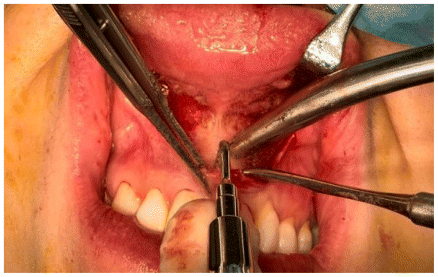

The osteotomy was composed of both horizontal and vertical segments (Figures 6,7,8). The horizontal segment was executed at the level of the piriform aperture, extending to the posterior maxilla and zygomatic buttress, with incisions made on the anterior and medial walls of the maxillary sinuses, while maintaining the cut just above the dental roots and following a slightly oblique inclination. This procedure was replicated on both the right and left sides. Subsequently, a vertical osteotomy was performed along the midline between the central incisors, corresponding to the median palatal suture, extending to the terminus of the bony palate at the midline. All osteotomies were carried out utilizing piezoelectric technology, with refinements made using a chisel by flexing (Figure 9).

Subsequent to the osteotomies, controlled activation of the MARPE device was executed to evaluate the resistance of the midline bone. The procedure was concluded with achieving hemostasis, irrigating with sterile saline solution, and suturing. (Figure 10)